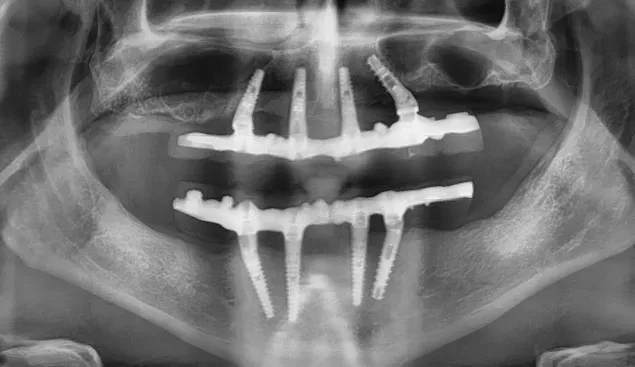

Le immagini radiografiche che seguono testimoniano alcune delle tante soluzioni tecniche che ho utilizzato per le arcate a carico immediato nel corso della mia carriera. Ogni caso presenta sfide diverse e richiede un approccio personalizzato.

Anche nei pazienti anziani con protesi mobili (dentiere) che presentano condizioni critiche dal punto di vista osseo, gli interventi di implantologia a carico immediato possono essere portati a termine con successo.

Tutto dipende dalle condizioni di salute generale e dall’anatomia residua. Non esiste un limite di età assoluto, ma solo una valutazione attenta del rapporto rischio-beneficio per ogni singolo paziente.